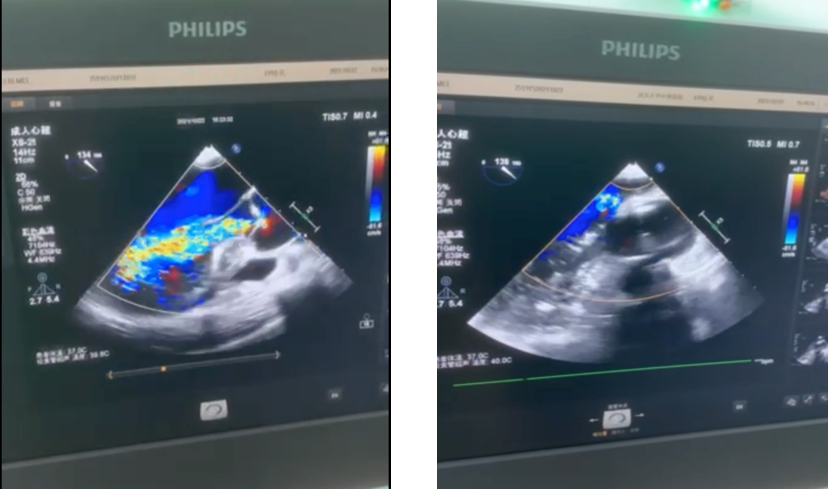

今天第三台J-Valve TAVR手术来自四川大学华西医院郭应强教授带领的多学科心脏团队,充分展现了J-Valve®在单纯主动脉瓣关闭不全经导管治疗治疗方面的独特性和巨大优势,郭应强教授毫无保留的分享了TAVR手术过程中手术的要点,处理心脏荷包的心得体会以及手术过程中团队配合导丝导管技术经验,获得与会专家一致好评。 手术在华西医院杂交手术室内完成,透视下选择心尖处肋间切开,TEE及DSA引导下行心尖穿刺,经心尖送入29mm J-Valve介入瓣膜并进行释放,瓣膜在定位件引导下进入主动脉瓣区域,释放瓣膜,造影及TEE现实瓣膜位置良好,无瓣周漏。从输送瓣膜到成功释放,整个过程不超过5分钟,手术全程患者生命征平稳,无出血,术后心脏功能明显好转,患者快速清醒,手术室内完成拔管,堪称一台J-Valve®介入瓣膜教学级的完美演绎。 下半场手术直播由空军军医大学附属西京医院徐学增教授,华中科技大学同济医学院附属同济医院魏翔教授,武汉亚洲心脏病医院华正东教授,浙江省人民医院崔勇教授,解放军总医院第一医学中心杨明教授,华中科技大学同济医学院附属协和医院陈澍教授共同主持。